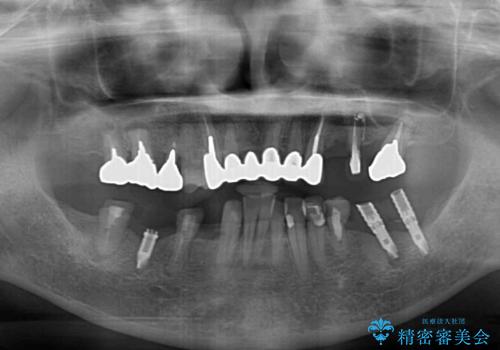

- 以前通院していた医院で、奥歯のインプラント埋入、前歯部のインビザライン矯正を行ったものの、そのまま放置してしまったとのことで来院された患者様です。

下顎前歯や上顎奥歯などをワイヤー装置により部分矯正を行い、歯列を整えた上でインプラン部分を含めてオールセラミッククラウンにて補綴治療を行うこととしました。

- 治療費の目安: 450万円(税込)費用は治療当時の料金となります

インプラント上の仮歯がボロボロになり、前歯に非常に負担のかかる状態であったため、早急に奥歯の仮歯を修復し、矯正治療、奥歯の補綴治療、前歯の補綴治療と順々に進めて行きました。